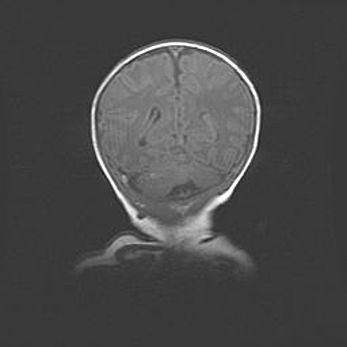

Лейкомаляция с кистозно-глиозной дегенерацией головного мозга.

Возраст: 2 месяца 25 дней

Вес: 6400 г

Окружность головы: 40 см

Срок гестации: 41 неделя

Лейкомаляцию относят к ишемически-гипоксическим повреждениям головного мозга, диагностируемым у новорожденных. При лейкомаляции в головном мозге обнаруживают очаги некроза, возникшие после тяжелой гипоксии и нарушения кровотока. В процессе морфогенеза очаги проходят три стадии: 1) развития некроза, 2) резорбции и 3) формирования глиозного рубца или кисты. Перивентрикулярная лейкомаляция (ПЛ) встречается примерно в 12% случаев среди новорожденных, обычно – у недоношенных детей, причем, частота ее зависит от массы, с которой младенец появился на свет. Наибольшее число малышей страдает лейкомаляцией, если масса при рождении 1500-2500 г.